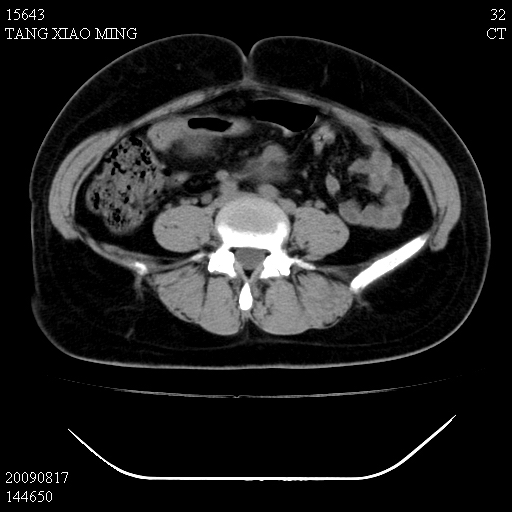

标题: CT21692:盆腔病变

女,33岁,右下腹痛2年余,既往宫外孕病史,如在我院手术,结果下周公布,

可能的诊断。1子宫内膜异位【子宫腺肌症并右卵巢巧克力囊肿】;2 右卵巢囊腺瘤。子宫肌瘤

1)考虑卵巢巧克力囊肿,不排除卵巢囊腺瘤。2)子宫肌瘤可能。

卵巢囊腺瘤,子宫肌瘤,直肠壁厚,不除外占位.